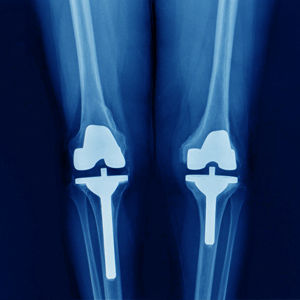

Kalça ProteziDiz Protezi